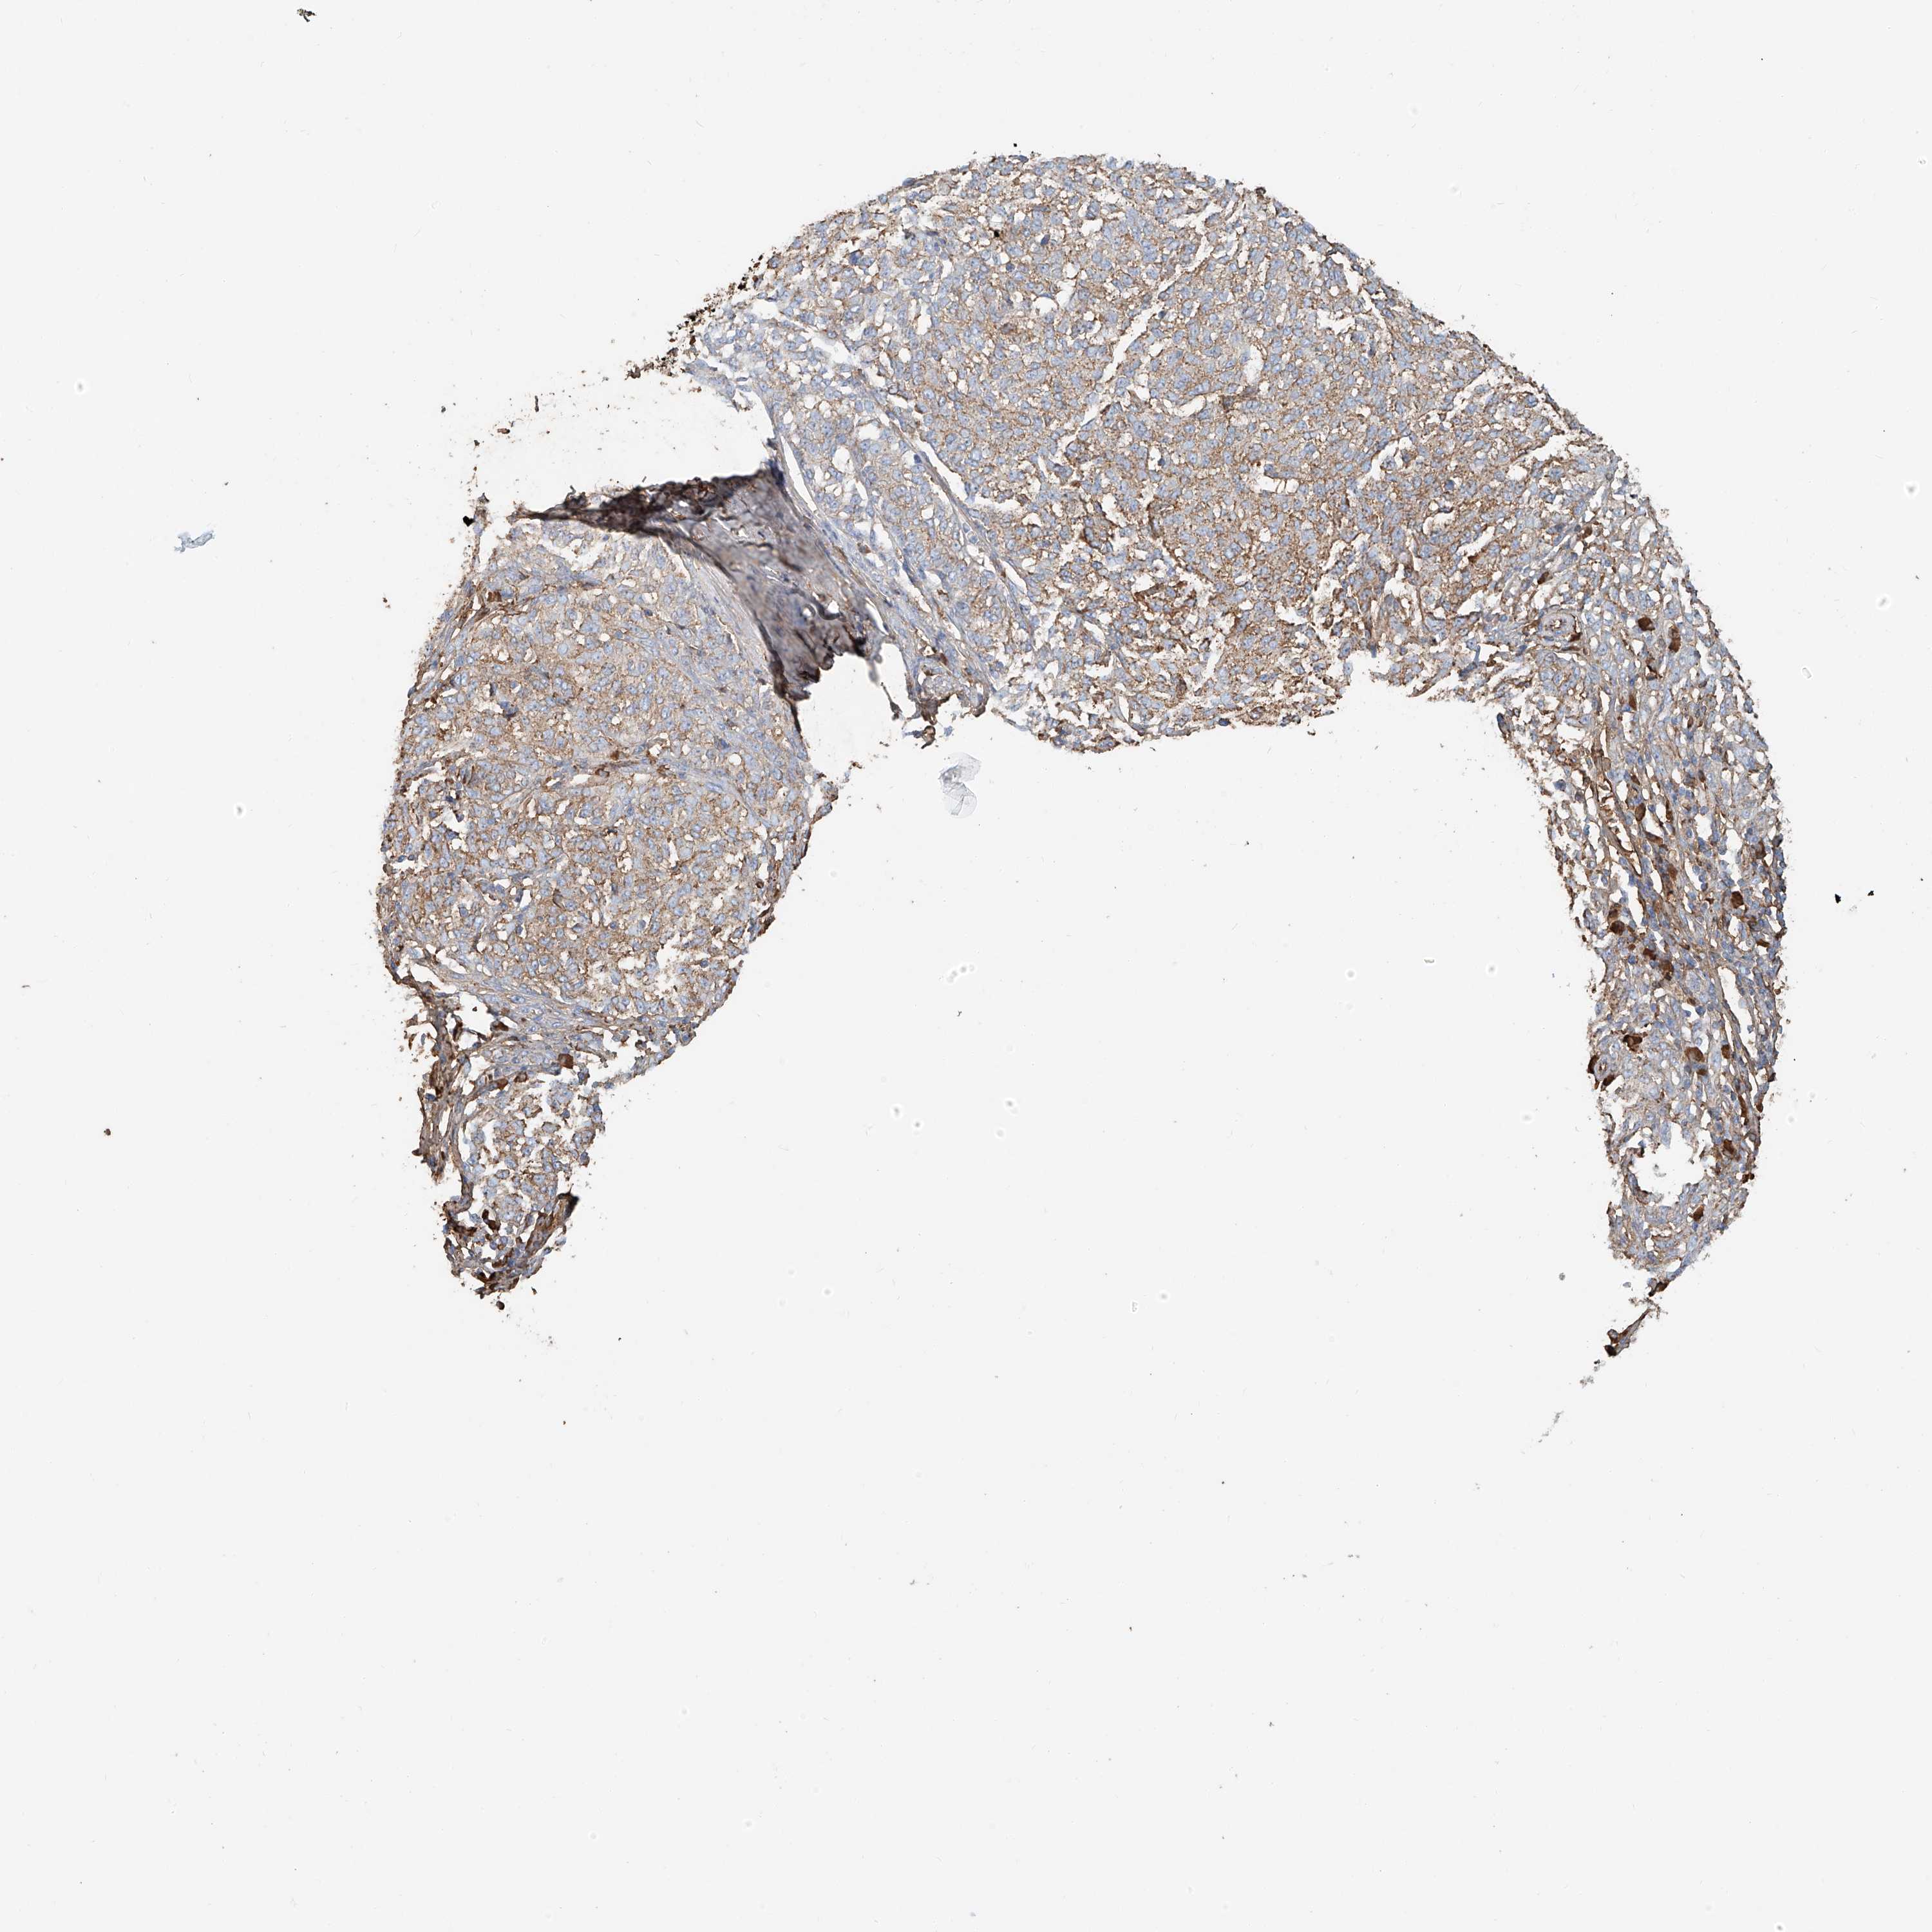

MELANOMA - Protein expressioni

A mouse-over function shows sample information and annotation data. Click on an image to view it in a full screen mode. Samples can be filtered based on level of antibody staining by selecting one or several of the following categories: high, medium, low and not detected. The assay and annotation is described here.

Note that samples used for immunohistochemistry by the Human Protein Atlas do not correspond to samples in the TCGA dataset.

Antibody stainingi

Antibody staining in the annotated cell types in the current human tissue is reported as not detected, low, medium, or high, based on conventional immunohistochemistry profiling in selected tissues. This score is based on the combination of the staining intensity and fraction of stained cells.

Each image is clickable and will lead to virtual microscopy that enables deeper exploration of all samples and also displays staining intensity scores, fraction scores and subcellular localization as well as patient and tissue information for each sample.

Antibody HPA030606

Staining

High

Medium

Low

Not detected

Intensity

Strong

Moderate

Weak

Negative

Quantity

>75%

75%-25%

<25%

None

Location

Nuclear

Cytoplasmic/membranous

Cytoplasmic/membranous,nuclear

Malignant melanoma, NOS

Malignant melanoma, Metastatic site